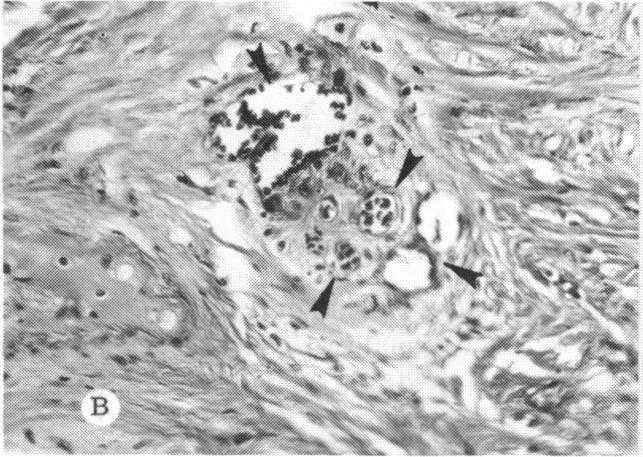

The clinical and histopathologic features of 29 eyes from 29 patients with central retinal vein occlusion (CRVO) are reported. A fresh or a recanalized thrombus was observed in each eye. This study considers the temporal aspects of the cases, and it notes the different morphologic features of the occlusion. These observations explain most of the variability of the changes observed in previous reports. We believe that these different features represent the various stages in the natural evolution of such a thrombus. The interval between CRVO and histopathologic study in our series ranged from six hours to more than 10 years. Local and systemic factors were reviewed and were found to be important in the pathogenesis of thrombus formation. Local diseases with a predisposing effect on CRVO included: glaucoma, papilledema, subdural hemorrhage, optic nerve hemorrhage, and drusen of the optic nerve head. Associated systemic diseases included: hypertension, cardiovascular and cerebrovascular disease, diabetes mellitus, and leukemia with thrombocytopenia. A fresh thrombus in the CRVO was observed in three (10.3%), and a recanalized thrombus in 26 eyes (89.7%). Endothelial-cell proliferation was a conspicuous feature in 14 (48.3%) of the eyes. Chronic inflammation in the area of the thrombus, and/or vein wall or perivenular area was observed in 14 (48.3%) of the eyes. Arterial occlusive disease was observed in seven eyes (24.6%). Cystoid macular edema was found in 26 (89.7%) of the eyes.

报告了29例视网膜中央静脉阻塞(CRVO)患者29只眼的临床和组织病理学特征。每只眼中均观察到新鲜或再通的血栓。本研究考虑了病例的时间因素,并记录了阻塞的不同形态学特征。这些观察结果解释了先前报告中观察到的变化的大部分变异性。我们认为这些不同特征代表了此类血栓自然演变的各个阶段。我们系列中CRVO与组织病理学研究之间的间隔时间从6小时到10多年不等。对局部和全身因素进行了回顾,发现它们在血栓形成的发病机制中很重要。对CRVO有 predisposing 作用的局部疾病包括:青光眼、视乳头水肿、硬膜下出血、视神经出血和视神经乳头玻璃膜疣。相关的全身疾病包括:高血压、心血管和脑血管疾病、糖尿病以及伴有血小板减少的白血病。在CRVO中观察到3只眼(10.3%)有新鲜血栓,26只眼(89.7%)有再通血栓。14只眼(48.3%)中内皮细胞增殖是一个显著特征。14只眼(48.3%)中观察到血栓区域、和/或静脉壁或静脉周围区域有慢性炎症。7只眼(24.6%)中观察到动脉闭塞性疾病。26只眼(89.7%)中发现黄斑囊样水肿。 (注:文中“predisposing”可能是“易患的”意思,但在专业医学语境中,可能有更准确特定含义,这里按常见理解翻译,具体含义需结合医学专业知识进一步确认。)